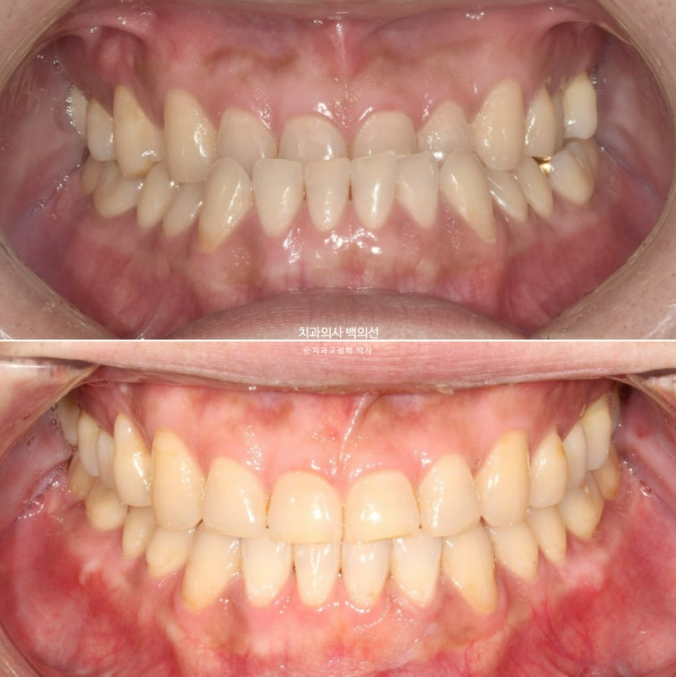

23.07~25.04

중심선은 잘 맞으며

어금니 교합은 좋습니다.

철사유지장치까지 부착된 모습입니다.

앞니 거꾸로 물리는 반대교합은 해소가 되었고